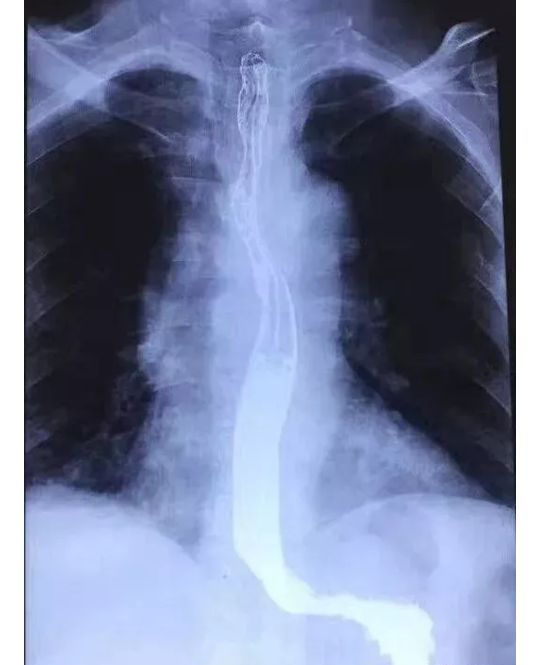

食道钡剂通过顺利,上段局部形态欠规整,管壁略僵硬。其他食管和胃十二指肠未见明显异常。放射科的医生拿不定主意,怀疑是不是上段食管癌?

进镜见喉炎,食管下段糜烂,食管距门齿20~35cm可见菜花状隆起,表面糜烂粗糙,覆厚白苔污秽苔,占据管腔1/3,内镜顺利通过,触之易出血,活检,质地脆,弹性差。作为消化内科的医生,几乎没有疑问,这就是食管癌,而且是晚期,临床表现。返病房,待病理。两天后病理检查的结果出来了:“食管”鳞状上皮黏膜慢性炎局部急性炎及上皮增生。这下子矛盾来了,这眼看着的食管癌,可是病理却连个不典型增生都没有发现,开刀?放疗?化疗?没有病理证实是万万不可能的!决定复查螺旋CT想了解食管病变壁外的情况。结果如下:

显示:食管异物!决定行胃镜再次检查,进镜见:食管上段竟然横挂着一根弯弯的骨头!这可不能随便取!万一骨头扎进了主动脉,贸然取出会当场大出血死人的!

因为已经做了胸部螺旋CT,联系放射科,经过仔细寻找,在食管的部位发现了骨头,虽然已经刺破食管,有了穿孔,万幸的却是骨头并没有在主动脉内,通过胃镜把这个骨头取了出来!